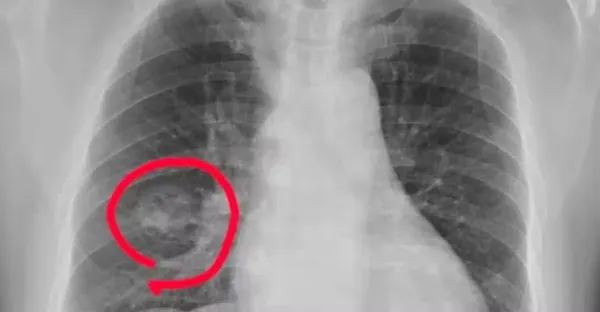

手腳出現 4 種異常,可能是得肺癌了,千萬不要大意

呂純弘 • 22K次觀看